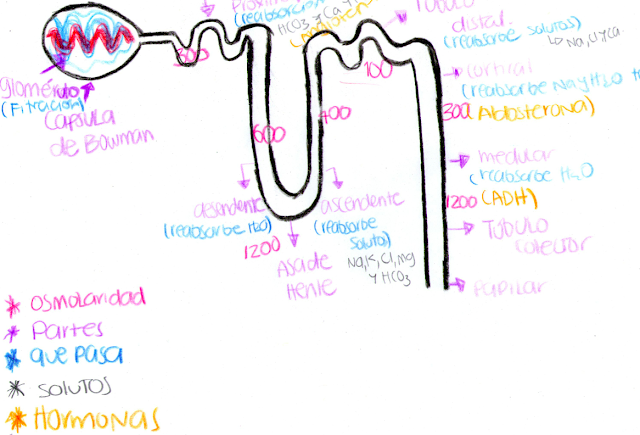

Transporte tubular (reabsorción y

excreción tubular).

Es

un sistema de túbulos conectados entre si y que su objetivo es especifico en

cada región; su finalidad es la modificación del líquido filtrado, bien

mediante la reabsorción de las sustancias esenciales para el organismo, desde

la luz tubular hacia los capilares sanguíneos.

Túbulo proximal: se

produce la reabsorción del 60-70% de la carga filtrada en el glomérulo. Este transporte

depende de la bomba de Na y K ATPasa.

Asa de Henle:

reabsorbe agua en la zona descendente y se reabsorben solutos (Na, K, Cl, Mg y

HCO3) en la zona ascendente.

Túbulo distal: este

segmento es impermeable al agua u si función principal pero reabsorbe Na, Cl y

Ca.

Túbulo colector:

tiene 3 zonas: la zona cortical se reabsorbe Na y agua y saca K gracias a la

acción de la aldosterona, en la zona medular se reabsorbe agua si hay ADH y la tercera porción es la papilar donde no

pasa nada.

La

osmolaridad va cambiando a lo largo del sistema tubular.

- Túbulo

proximal: se reabsorbe agua y solutos o sea que la osmolaridad queda igual.

- Asa

de Henle: en la parte descendente se reabsorbe agua o sea que sube la

osmolaridad y en la parte ascendente se reabsorben solutos así que la

osmolaridad baja.

- Túbulo

distal: se reabsorben solutos o sea que la osmolaridad baja

-

Túbulo colector: en la parte cortical se

reabsorbe agua y solutos o sea que queda igual la osmolaridad y en el túbulo

colector medular se reabsorbe agua o sea que sube la osmolaridad.